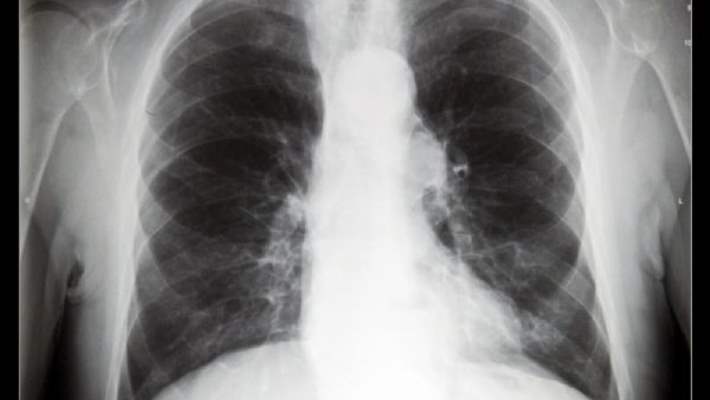

Akciğer Kanseri Taramasında Kullanılan Yöntemler

Günümüzde bilgisayarlı tomografiler çok daha ince kesitler alabilen, ileri teknolojili aygıtlardır. Tomografi ile çok iyi bir şekilde akciğer tanısı konulabilir.

MR ise her hastada gerekmez. Ancak çok özel durumlarda MR çektirmek gerekebilir. Örneğin, akciğer kanserinin belli alanlara yayılmasını MR tomografiden daha iyi gösterir. Ancak bu hasta grubu yüzde 5’in altındadır. Dolayısıyla pratikte akciğer kanseri tanısında en önemli radyolojik tanı yöntemi tomografidir.